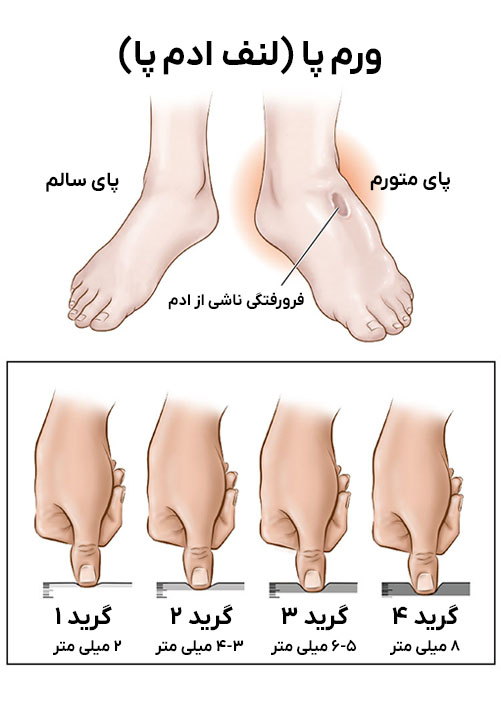

در تصویر میتوانید درجهبندیهای مختلف ورم پا در سالمندان را مشاهده کنید.

ادم (Edema) به تجمع غیرطبیعی مایع در بافتهای بدن گفته میشود که نتیجهاش تورم در نواحی مختلف و خصوصا در پاها و قوزکها است. اما بیماری لنف ادم پا (Lymphedema) نوع خاصی از ادم است که بهدلیل انسداد یا اختلال در سیستم لنفاوی ایجاد میشود؛ یعنی زمانی که بدن قادر به تخلیه مایعات لنفی از بافتها نیست.

این نوع ورم معمولاً مزمن، غیرقابل فشرده شدن و سفتتر از ادم معمولی است و در صورت درمان نشدن میتواند منجر به تغییر شکل اندام شود. علائم لنف ادم شامل:

- احساس سنگینی

- سفتی پوست

- کاهش انعطافپذیری مفصل

- ضخیم شدن پوست (در موارد پیشرفته و حاد)

از نشانههای شایع ورم پاهای سالمندان میتوان به تورم قابلمشاهده در قوزک و ساق پا، احساس سنگینی، درد خفیف و رد فرو رفتگی انگشت روی پوست اشاره کرد. در موارد پیشرفته ممکن است پوست براق یا ملتهب شود.